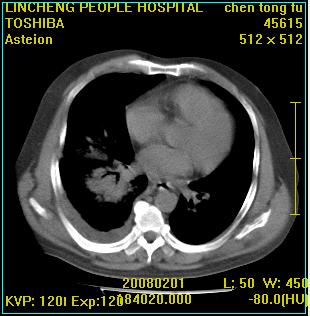

标题: CT11942:男性,62岁。右肺的病变 [打印本页]

患者,男性,62岁。主因头晕,发热,咳嗽6天,高热达39度,esr19mm/h,wbc 3.9×10 9/l

右肺大叶性肺炎,胸腔积液。建议痰检。

实变区见空气支气管征,支气管通畅,考虑为大叶性肺炎,右侧少量胸水

1)考虑为:右肺感染性病变。建议:抗炎治疗复查。2)右侧少量胸腔积液。

考虑为右肺大叶性肺炎,胸腔积液,建议必要时纤维支气管镜检查,以排除肿瘤性病变。

右肺炎症并右侧胸腔少量积液。